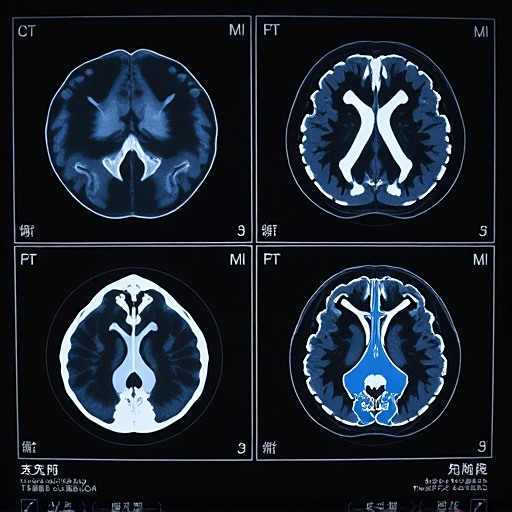

影像学检查如X光、超声或MRI可能会用于评估内脏器官受累情况。特别是当怀疑有心包炎、胸膜炎或神经系统受累时,这些检查能提供重要信息。